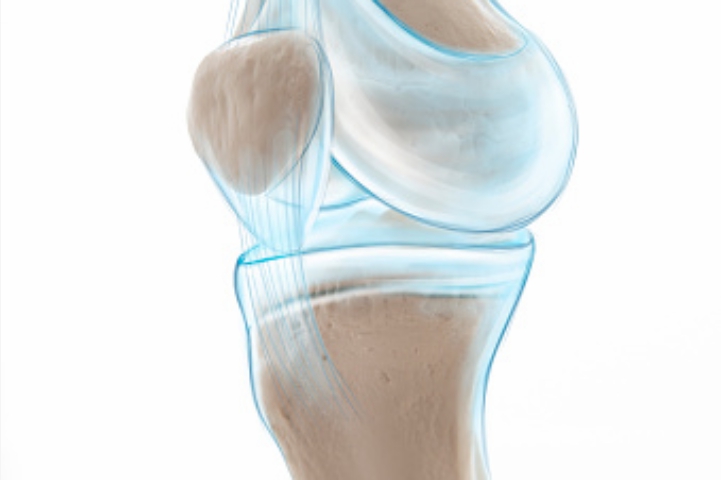

2. 콘드로이친 효능 연골 재생

콘드로이친은 연골 손상을 막을 뿐만 아니라 손상된 연골의 주요 성분인 연골세포를 재생시켜 연골 기능을 향상해 주는 역할을 합니다. 연골 손상으로 고통을 호소하는 사람들에게 도움이 됩니다.